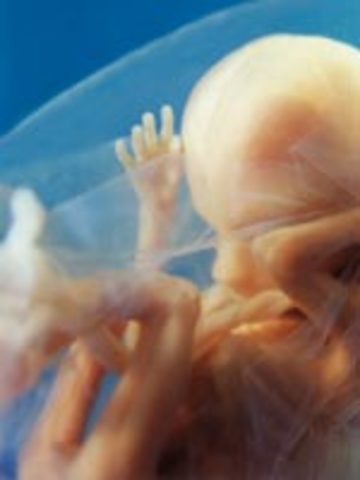

week 5

Amniotic fluid is building up. The embryo starts to grow.

• week 6

week 6

Embryo is about 8 mm in length. Spinal cord begining to close.

• week 7

week 7

One chamber of the heart is beating.arms and legs beging to form.

• week 8

week 8

Baby starts to move. Face is beginging to take shape.

• week 9

week 9

Fingers and toes are formed. nose and upper lip also start to form.